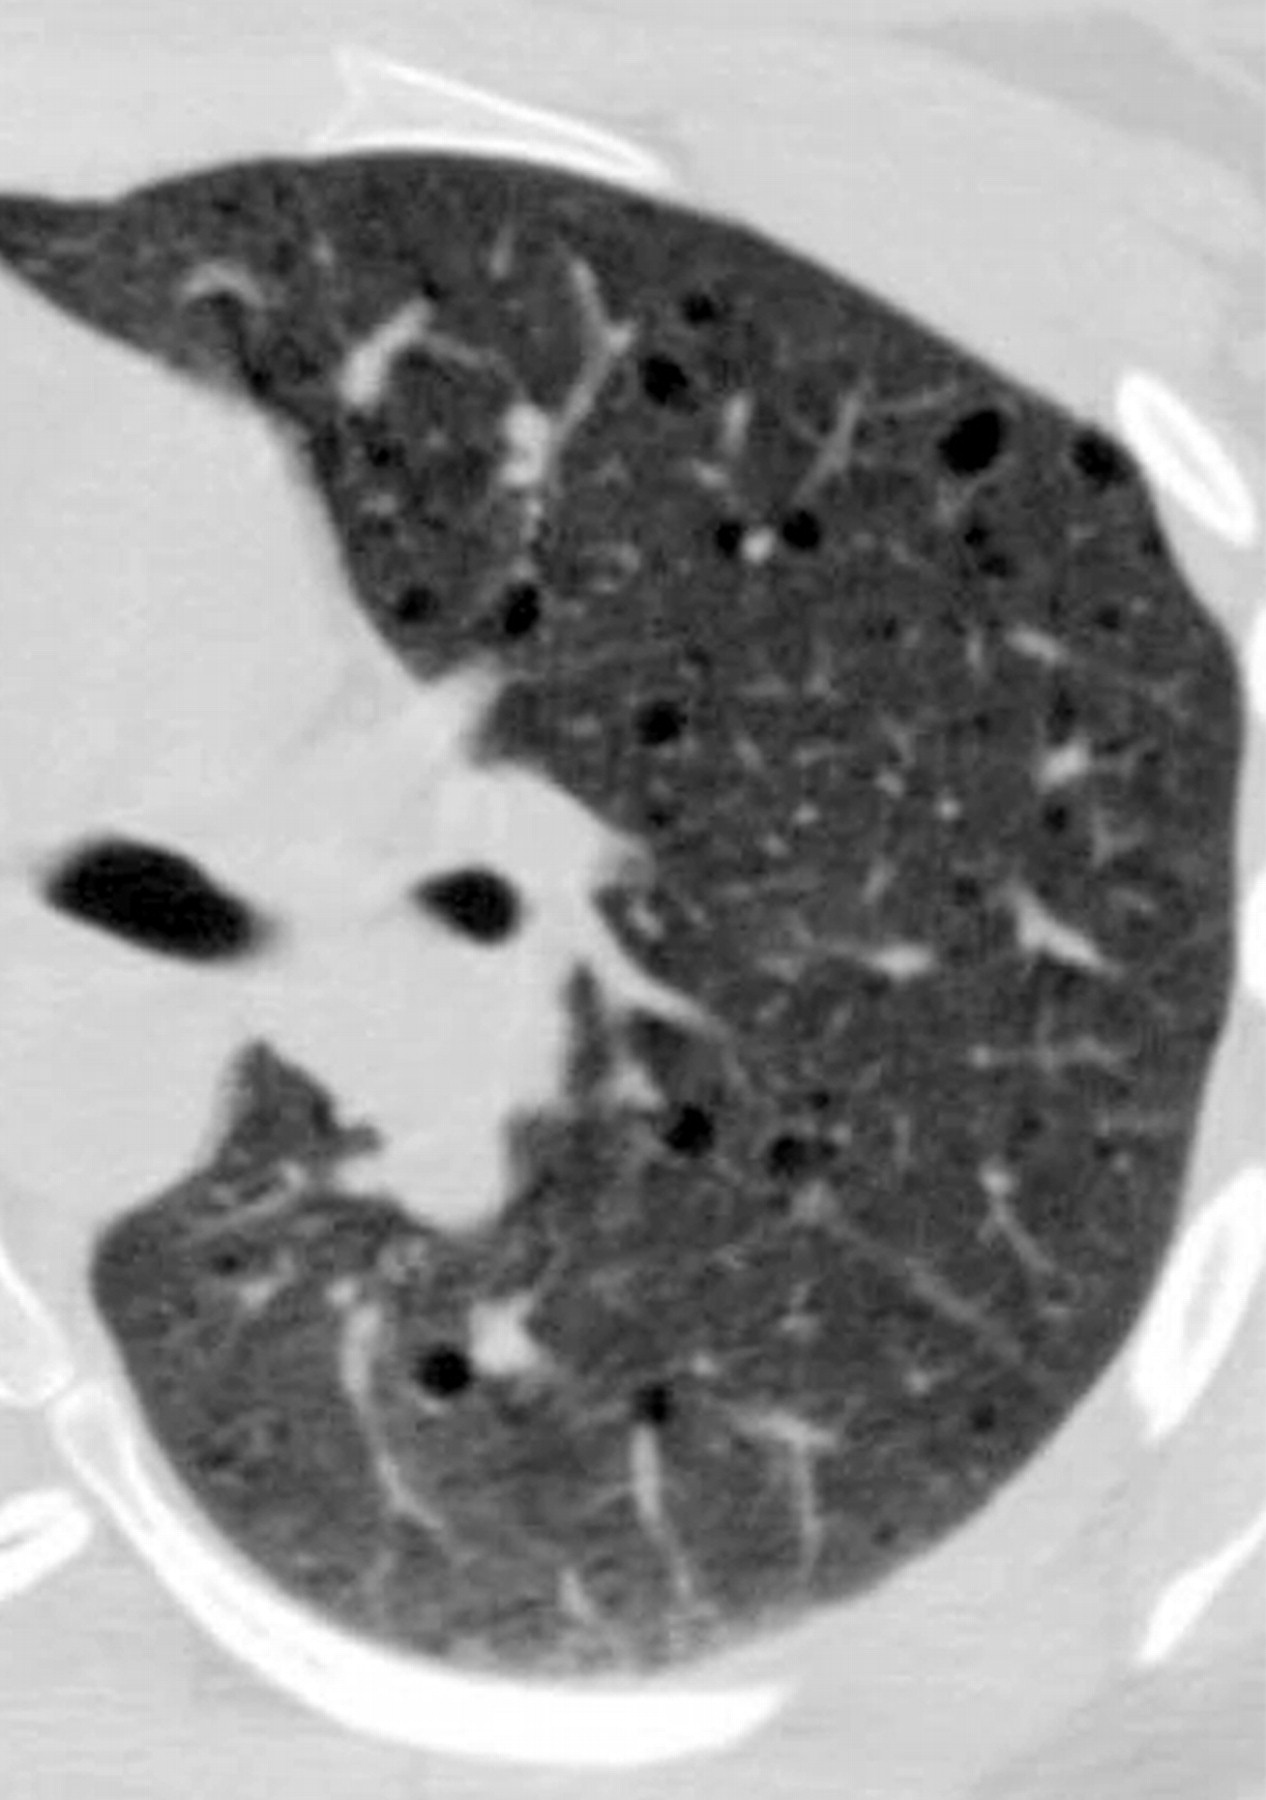

лимфангиолейомиоматоз

Типичный пример патологии при которой основным патерном являются кисты - :

Лимфангиомиоматоз.

Из архива AFIP. Лимфангиолейомиоматоз.

Лимфангиолейомиоматоз.